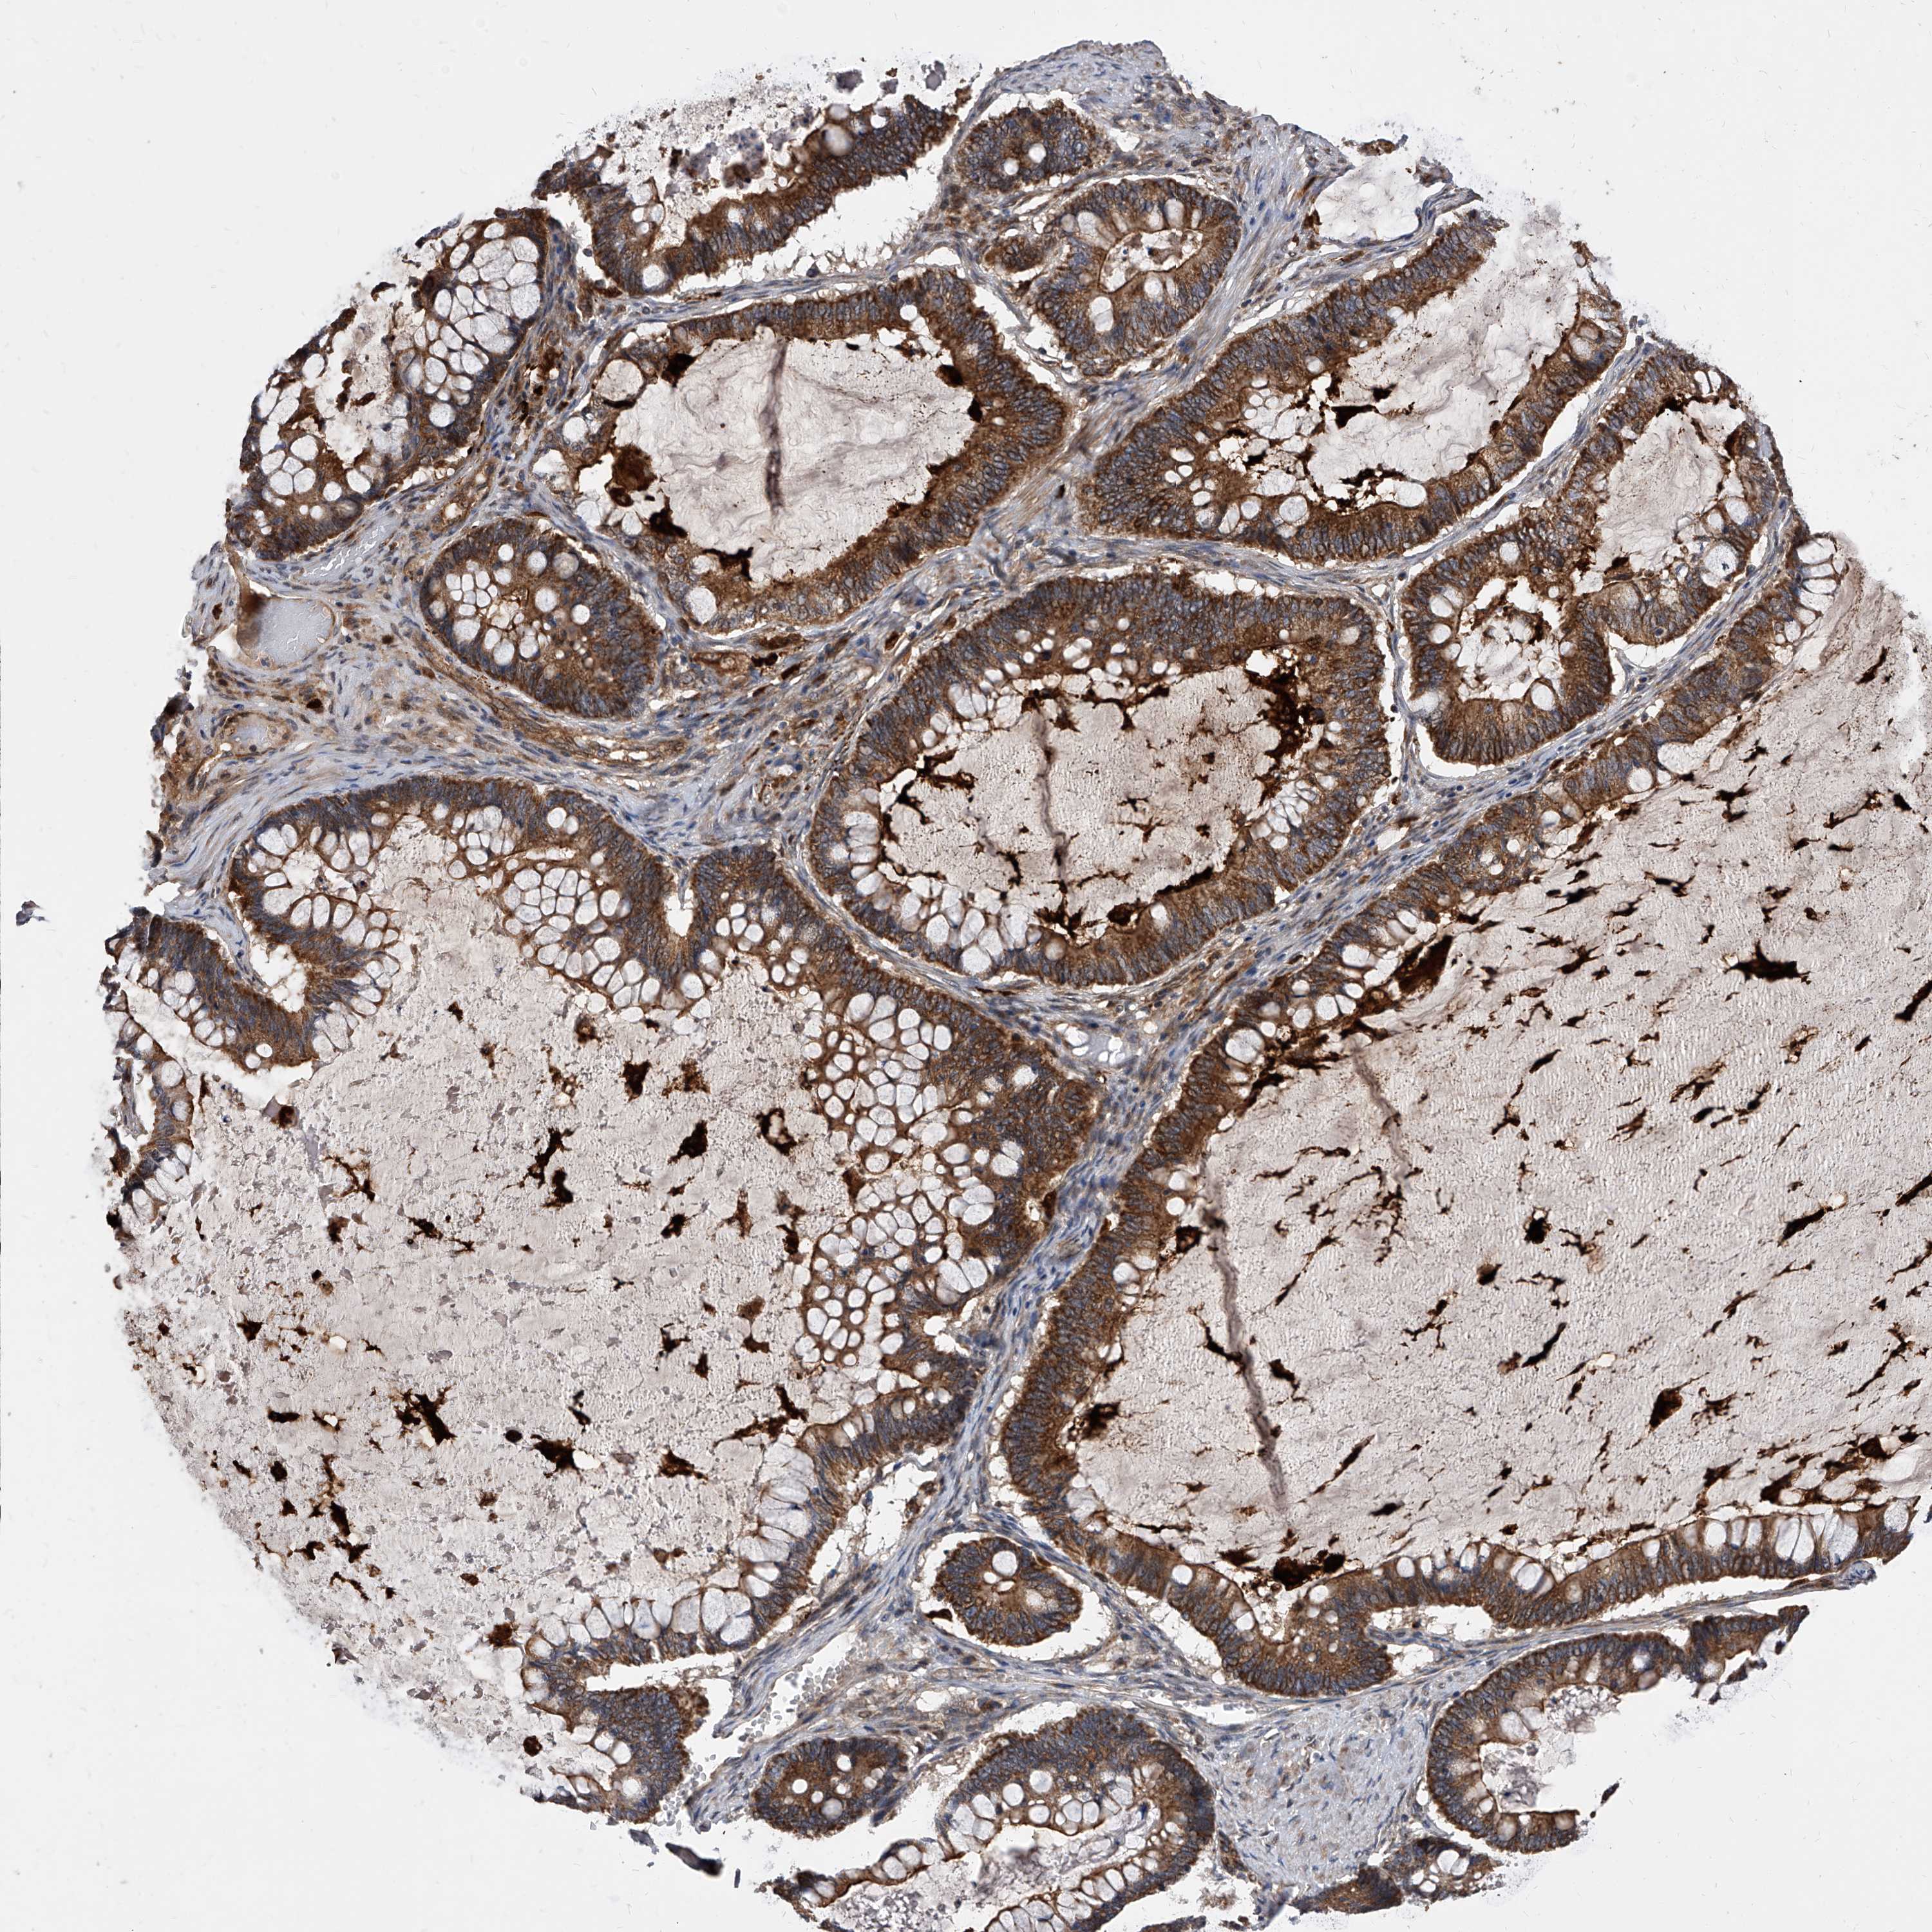

OVARIAN CANCER - Protein expressioni

A mouse-over function shows sample information and annotation data. Click on an image to view it in a full screen mode. Samples can be filtered based on level of antibody staining by selecting one or several of the following categories: high, medium, low and not detected. The assay and annotation is described here.

Note that samples used for immunohistochemistry by the Human Protein Atlas do not correspond to samples in the TCGA dataset.

Antibody stainingi

Antibody staining in the annotated cell types in the current human tissue is reported as not detected, low, medium, or high, based on conventional immunohistochemistry profiling in selected tissues. This score is based on the combination of the staining intensity and fraction of stained cells.

Each image is clickable and will lead to virtual microscopy that enables deeper exploration of all samples and also displays staining intensity scores, fraction scores and subcellular localization as well as patient and tissue information for each sample.

Antibody HPA029242

Staining

High

Medium

Low

Not detected

Intensity

Strong

Moderate

Weak

Negative

Quantity

>75%

75%-25%

<25%

None

Location

Nuclear

Cytoplasmic/membranous

Cytoplasmic/membranous,nuclear

Cystadenocarcinoma, serous, NOS

Carcinoma, endometroid

Cystadenocarcinoma, mucinous, NOS

Carcinoma, NOS